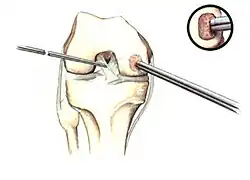

Intact lesions

If non-surgical measures are unsuccessful, drilling may be considered to stimulate healing of the subchondral bone. Arthroscopic drilling may be performed by using an antegrade (from the front) approach from the joint space through the articular cartilage, or by using a retrograde (from behind) approach through the bone outside of the joint to avoid penetration of the articular cartilage. This has proven successful with positive results at one-year follow-up with antegrade drilling in nine out of eleven teenagers with the juvenile form of OCD,[53] and in 18 of 20 skeletally immature people (follow-up of five years) who had failed prior conservative programs.[54]